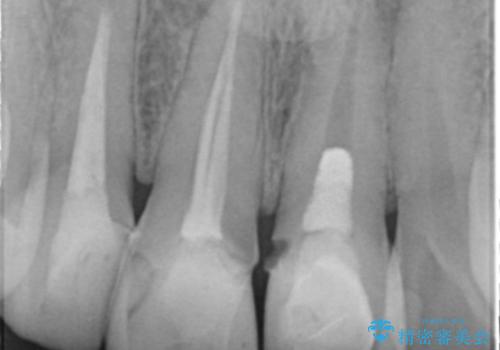

視診・X線検査・歯周組織検査より下記のような問題が列挙され、長期的な予後を見込むために一つづつ問題の解決を計ります。

・不十分な根管治療 →マイクロスコープを用いる精密根管医療

・歯の変色 →ジルコニアクラウンの製作

・歯肉縁下カリエス →部分矯正による歯の挺出・歯周外科